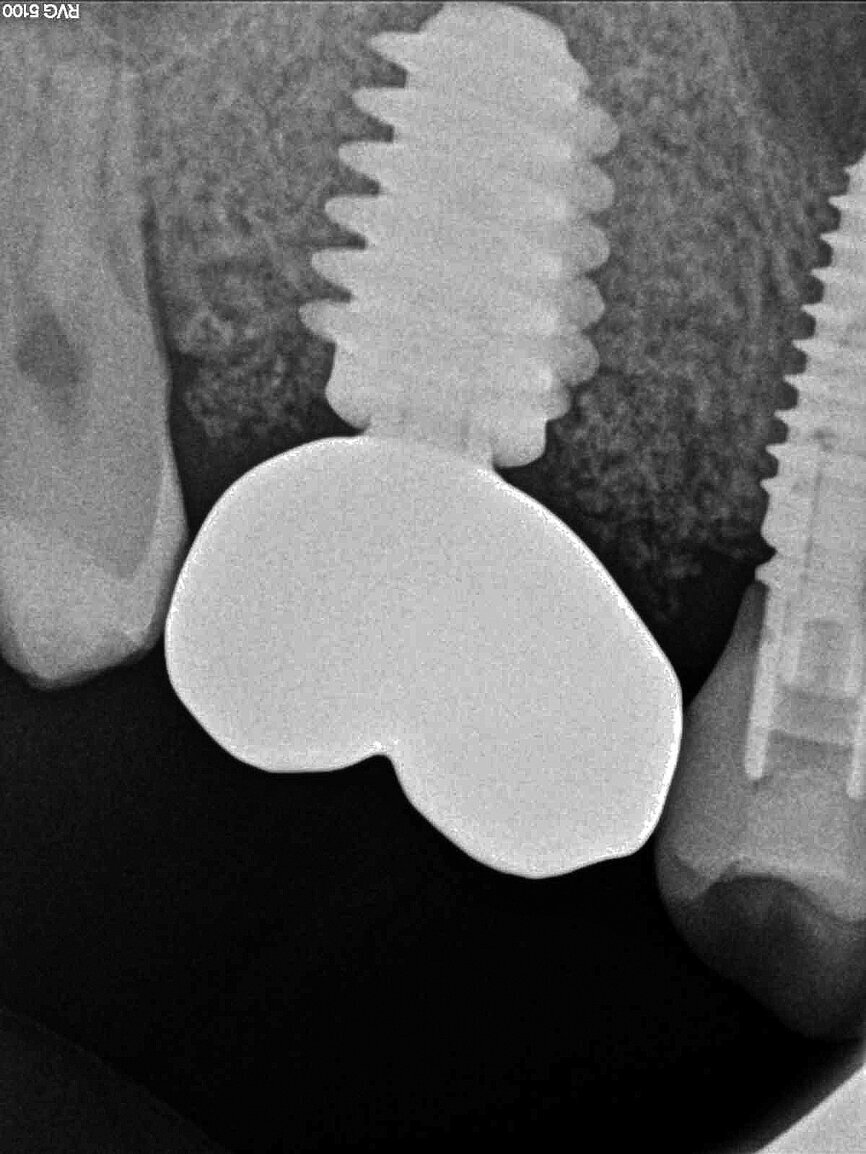

Once the implant bed had been prepared, a 7 × 10 mm implant (AnyRidge) was placed. After placement, the ISQ (Implant Stability Quotient) was measured with a stability meter (Mega ISQ, MegaGen), and the value was 72. According to the ISQ scale, this represents high stability (Fig. 6b). A 10 × 7 mm healing screw (AnyRidge) was placed, along with a plug of A-PRF (advanced platelet-rich fibrin; PRF process by Choukroun) in order to accelerate the healing process, and sutured with 4/0 polypropylene (Hu-Friedy; Figs. 7–10). After the surgical procedure, the White Clinic postoperative protocol was applied: application for eight minutes of the ATP38 laser (Swiss Bio Inov), based on the principle of Low Level Laser Therapy that acts on the cellular metabolism and provides a better and faster postoperative healing. The patient was instructed to use a 0.2% hyaluronic acid gel (Gengigel, Ricerfarma) and 0.1% hyaluronic acid mouthwash (Gengigel First-aid, Ricerfarma) for one week after surgery, with the goal of accelerating the healing process. One week after surgery, the sutures were removed, ozone was used to disinfect the area around the implant, and the ATP38 was applied for eight minutes to promote healing.

In March 2018, four months after the surgery, the prosthetic phase was started. An impression was taken with an intraoral scanner (CS 3600, Carestream Dental) using scan bodies for an impression at the implant head (MegaGen; Figs. 11a & b). The information was sent to the Anatomic Lab, where a crown was designed using a CAD programme. After the design of the crown had been finished, the information was sent to a milling machine (Amann Girrbach) and the crown was milled (Fig. 12). One week after the preparation, the definitive crown in monolithic zirconia was attached and the occlusion tested using T-Scan technology (Tekscan; Figs. 13a–c & 14).